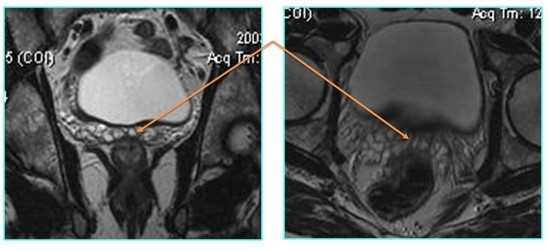

МРТ простаты что показывает

МРТ: рак простаты Т2а и Т3а (стрелки указывают на вовлеченность капсулы в опухолевый процесс)

А - магнитно-резонансная томограмма демонстрирует неровность контура капсулы левой доли простаты с распространением мягкотканного компонента за ее пределы (стрелка), Т2 ВИ. В - изображение после динамического введения гадолиния. С - после обработки компьютерной программой - явное усиление интенсивности МР-сигнала в зоне патологии, типичное для неопластического перерождения